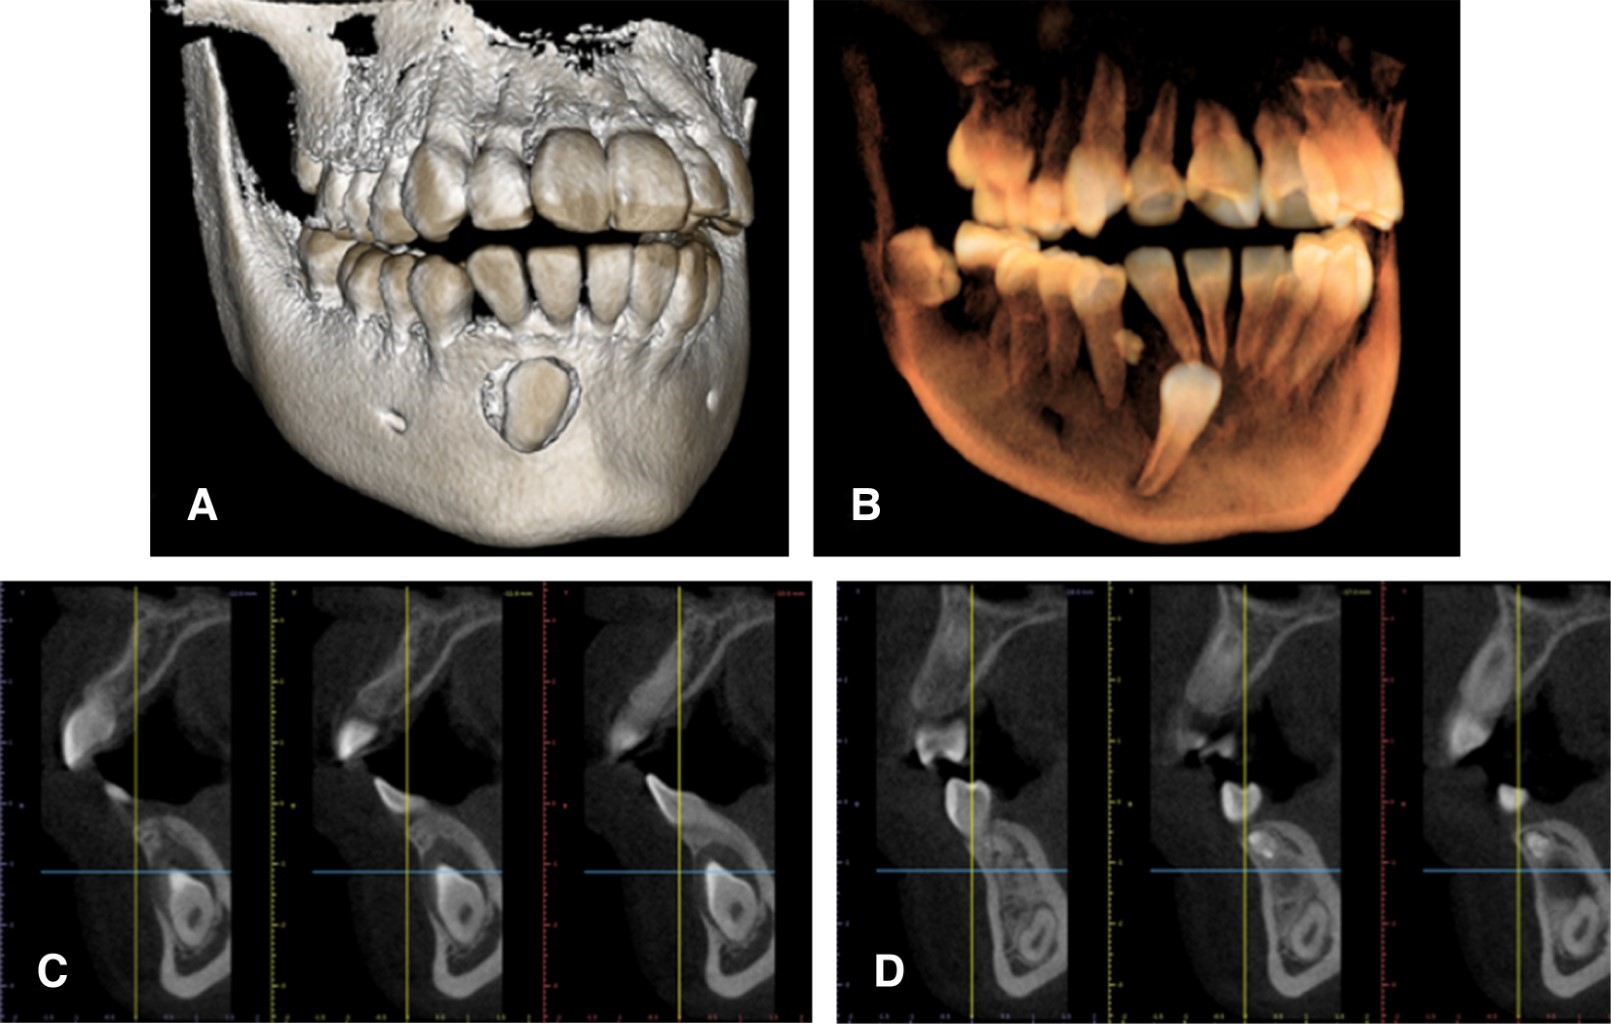

En la radiografía panorámica se observó una zona radiolúcida alrededor de la corona del órgano dentario 43, con márgenes bien delimitados que emergen de la unión amelocementaria, con medida aproximada de 15 mm de diámetro; también se identificó una imagen independiente a la anterior, la cual es mixta radiolúcida y radiopaca con bordes bien definidos, mesial al órgano dentario 44, a nivel de tercio medio radicular (Figura 1). La tomografía computarizada (TC) reveló que la cavidad quística rodeaba la corona del órgano dentario 43 (Figura 2). Por las características de los exámenes radiográficos, el diagnóstico presuntivo de la entidad alrededor de la corona del órgano dentario 43 fue un quiste dentígero, y el de la entidad mesial al 44 fue un odontoma. Se planificó una cirugía con el objetivo de realizar la escisión quirúrgica completa de ambas entidades y efectuar estudio histopatológico para corroborar su diagnóstico y, de ser posible, la colocación de un aditamento de ortodoncia en el órgano dentario 43 para su futura tracción y correcto posicionamiento en la arcada.

Figura 1

Figura 2